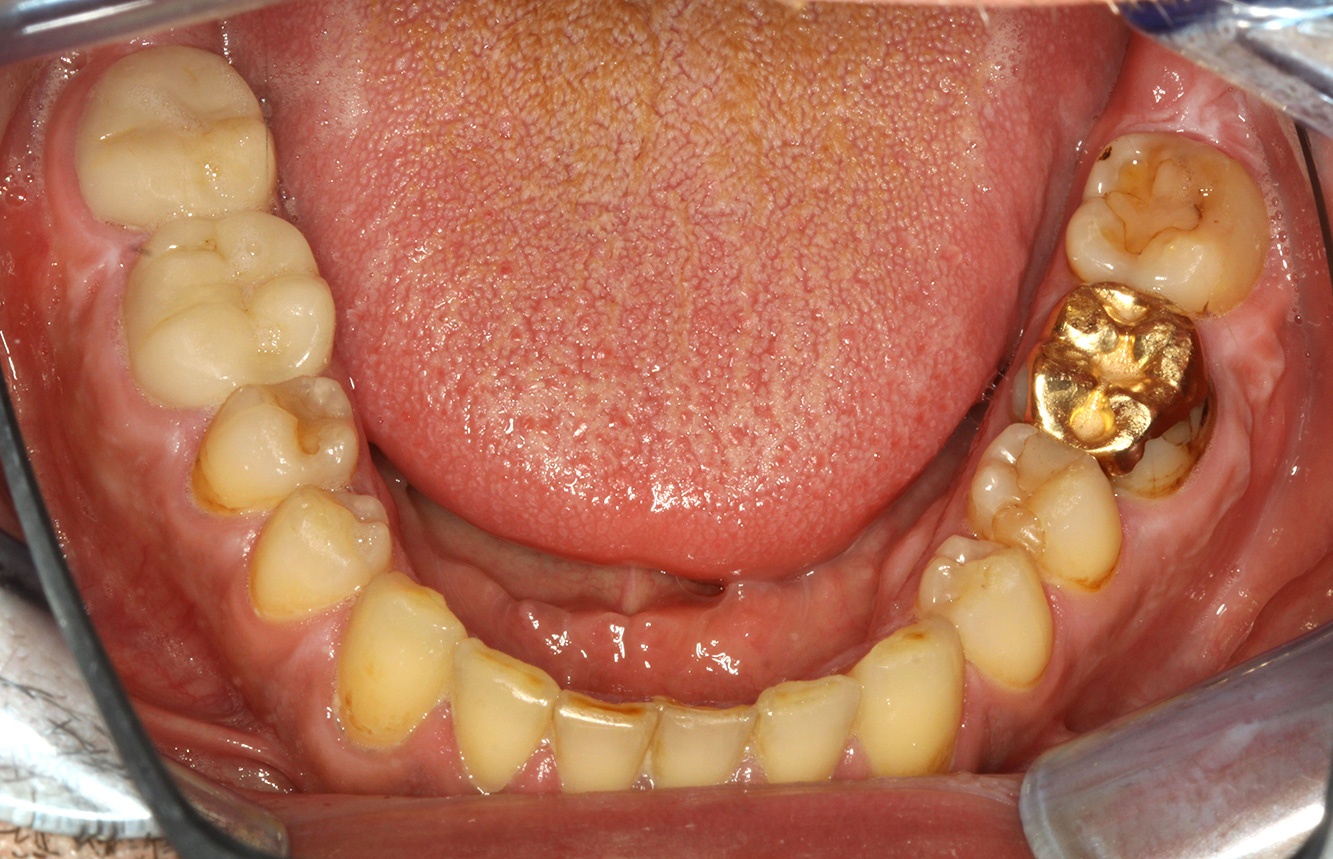

Cazuri pacienți conform IPC

Următoarele studii de caz* acestea au rolul să ilustreze interacțiunea dintre necesitățile și factorii de risc definiți pentru IPC, precum și efectele factorilor individuali.

Pacient cu endocardită cu leziuni carioase active

Pacientul are 39 de ani și a suferit anterior o înlocuire a valvei aortice din cauza unei insuficiențe de valvă și a unei endocardite. ASS 100 este administrat în mod regulat ca anticoagulant. În ceea ce privește stilul de viață, dieta pacientului este clasificată ca fiind favorizantă pentru carii, datorită consumului regulat de alimente zaharoase și a faptului că se consumă șase până la șapte mese pe zi. Sănătatea orală a pacientului indică un risc moderat de carii, cu leziuni active. Riscul de parodontoză este scăzut, dar gingivita este prezentă. Se fac următoarele recomandări pentru tratamentul profilactic. mai multe